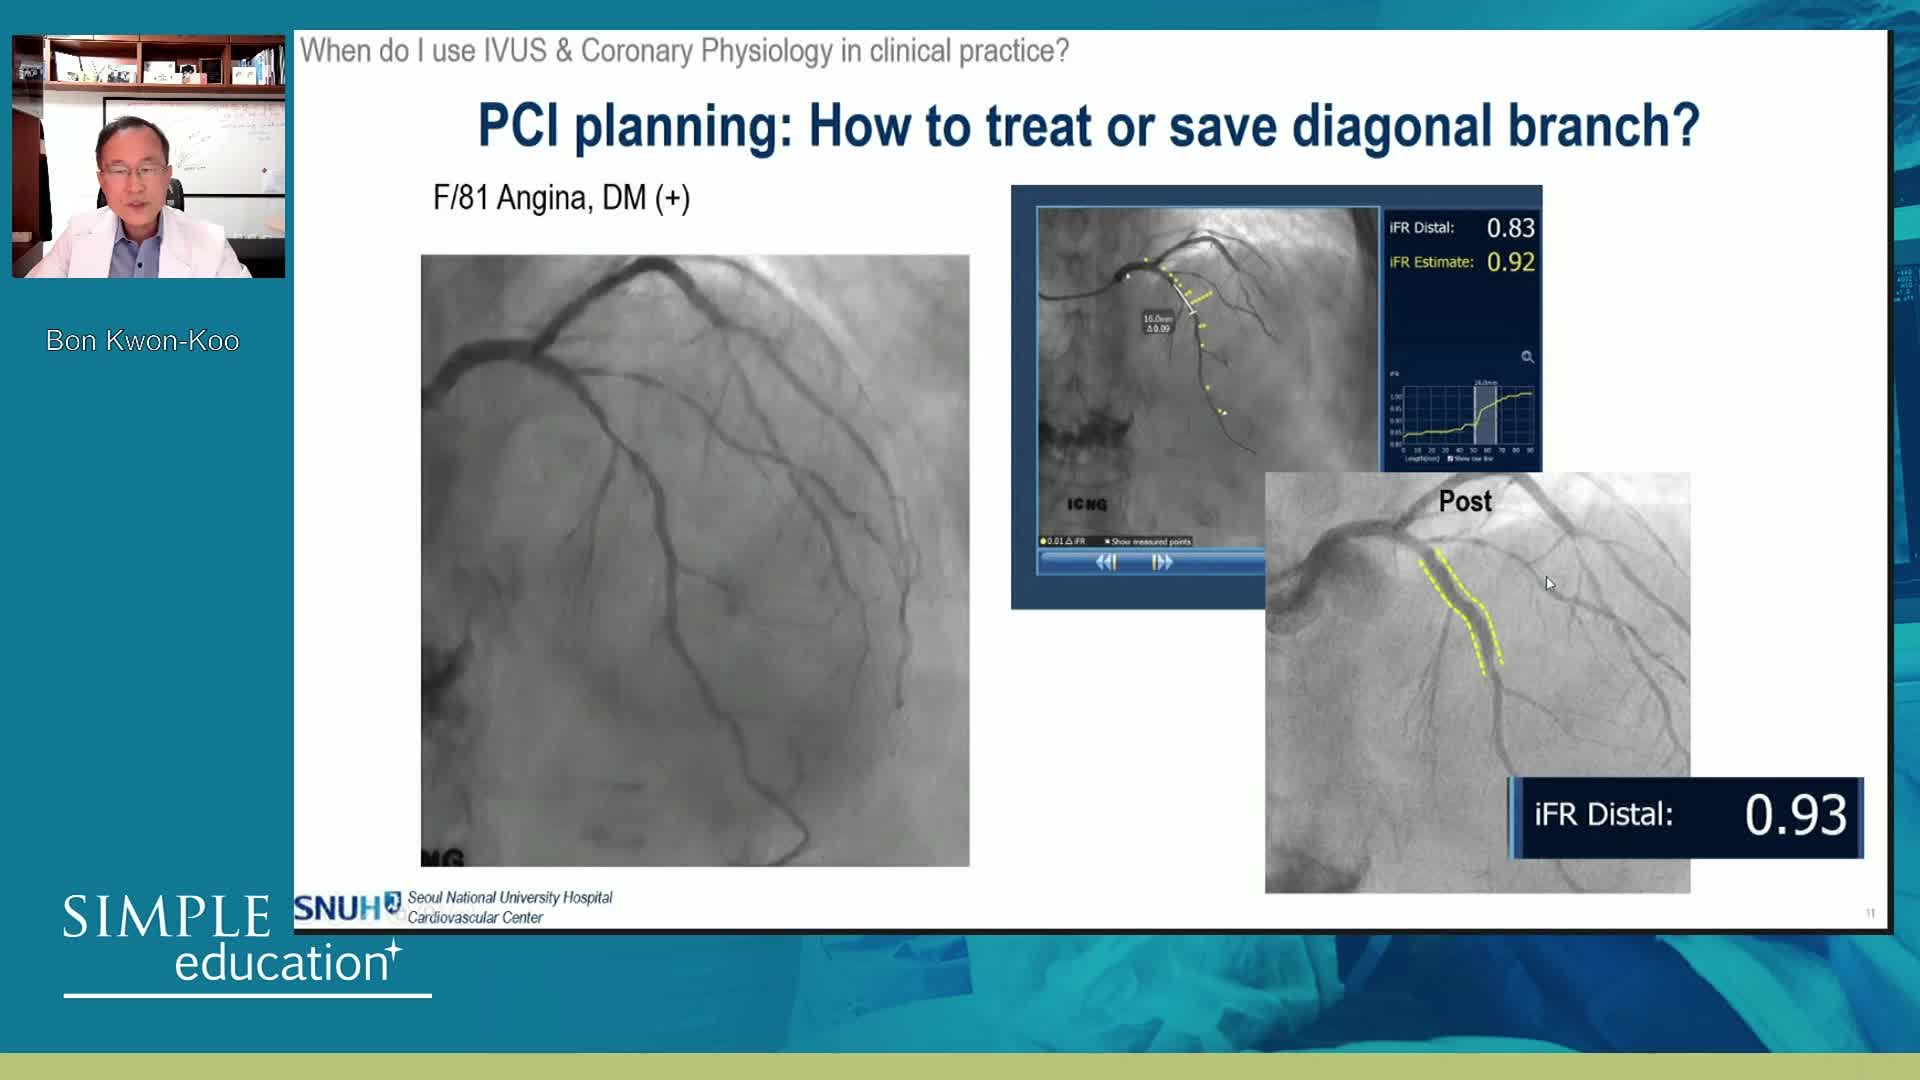

Coronary Bifurcations: An Update on Diagnosis, PCI planning and Imaging and PhysiologyGuidance - Dr Dejan Milasinovic